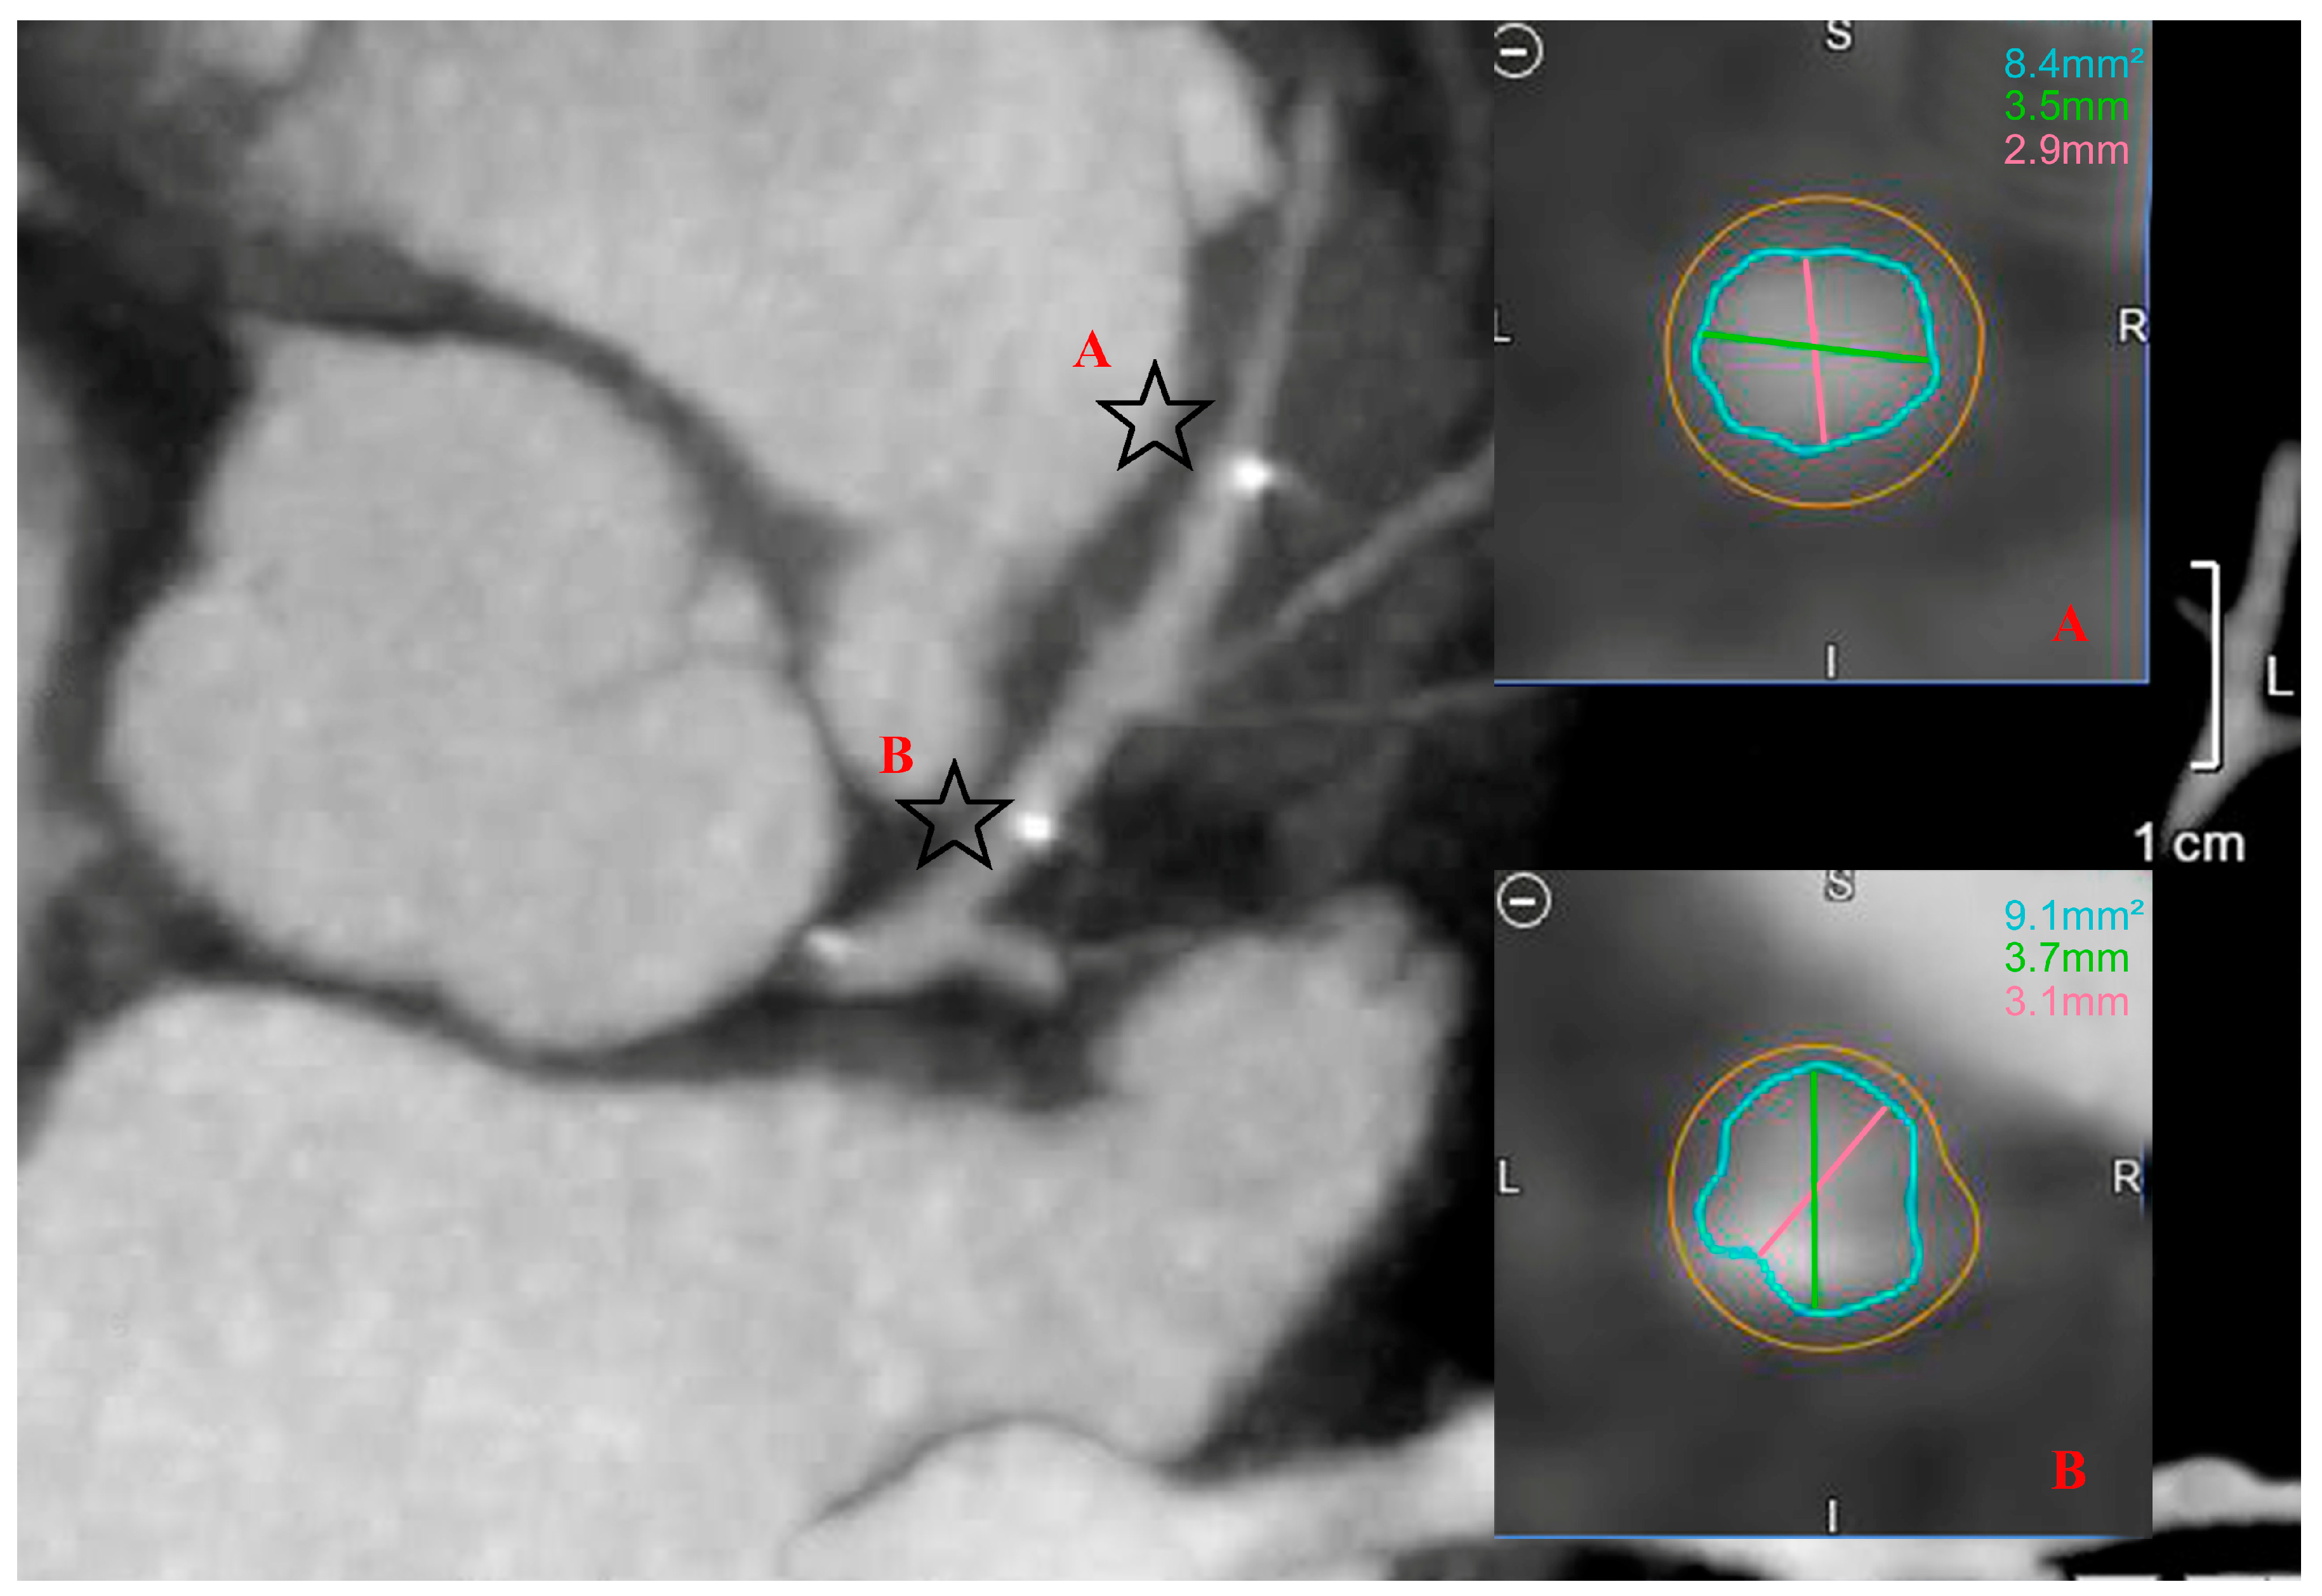

3.2. Clinical and Radiological Outcome